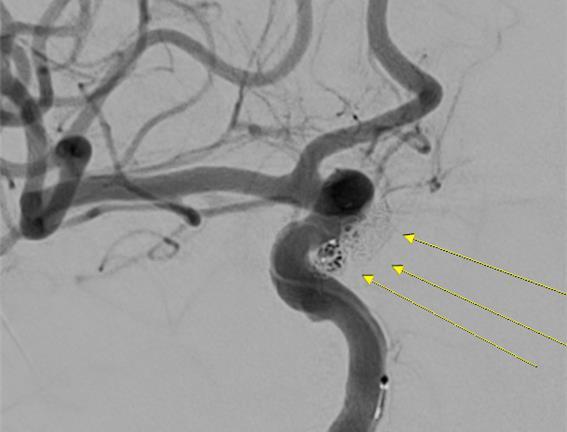

환자 A 씨의 파열된 대뇌동맥류 코일색전술 사진(센텀종합병원 재판매 및 DB금지)

의료진은 A 씨에 대해 응급 코일 색전술을 시행했다. 코일 색전술은 개두술(머리를 직접 절개하는 수술) 없이 혈관 내 접근을 통해 뇌동맥류를 치료하는 비침습적 수술법이다. 다리 대퇴부나 팔의 혈관을 통해 미세한 도관(카테터)을 삽입한 뒤 이를 뇌혈관에 위치시키고 동맥류 내부에 특수 금속 코일을 채우는 것이다.

이 수술법은 혈류 흐름을 차단해 추가 출혈을 예방할 뿐만 아니라 미세 침습 수술이라 회복 속도가 빠르고, 필요할 경우 추가적인 색전술을 시행할 수 있는 장점이 있다.